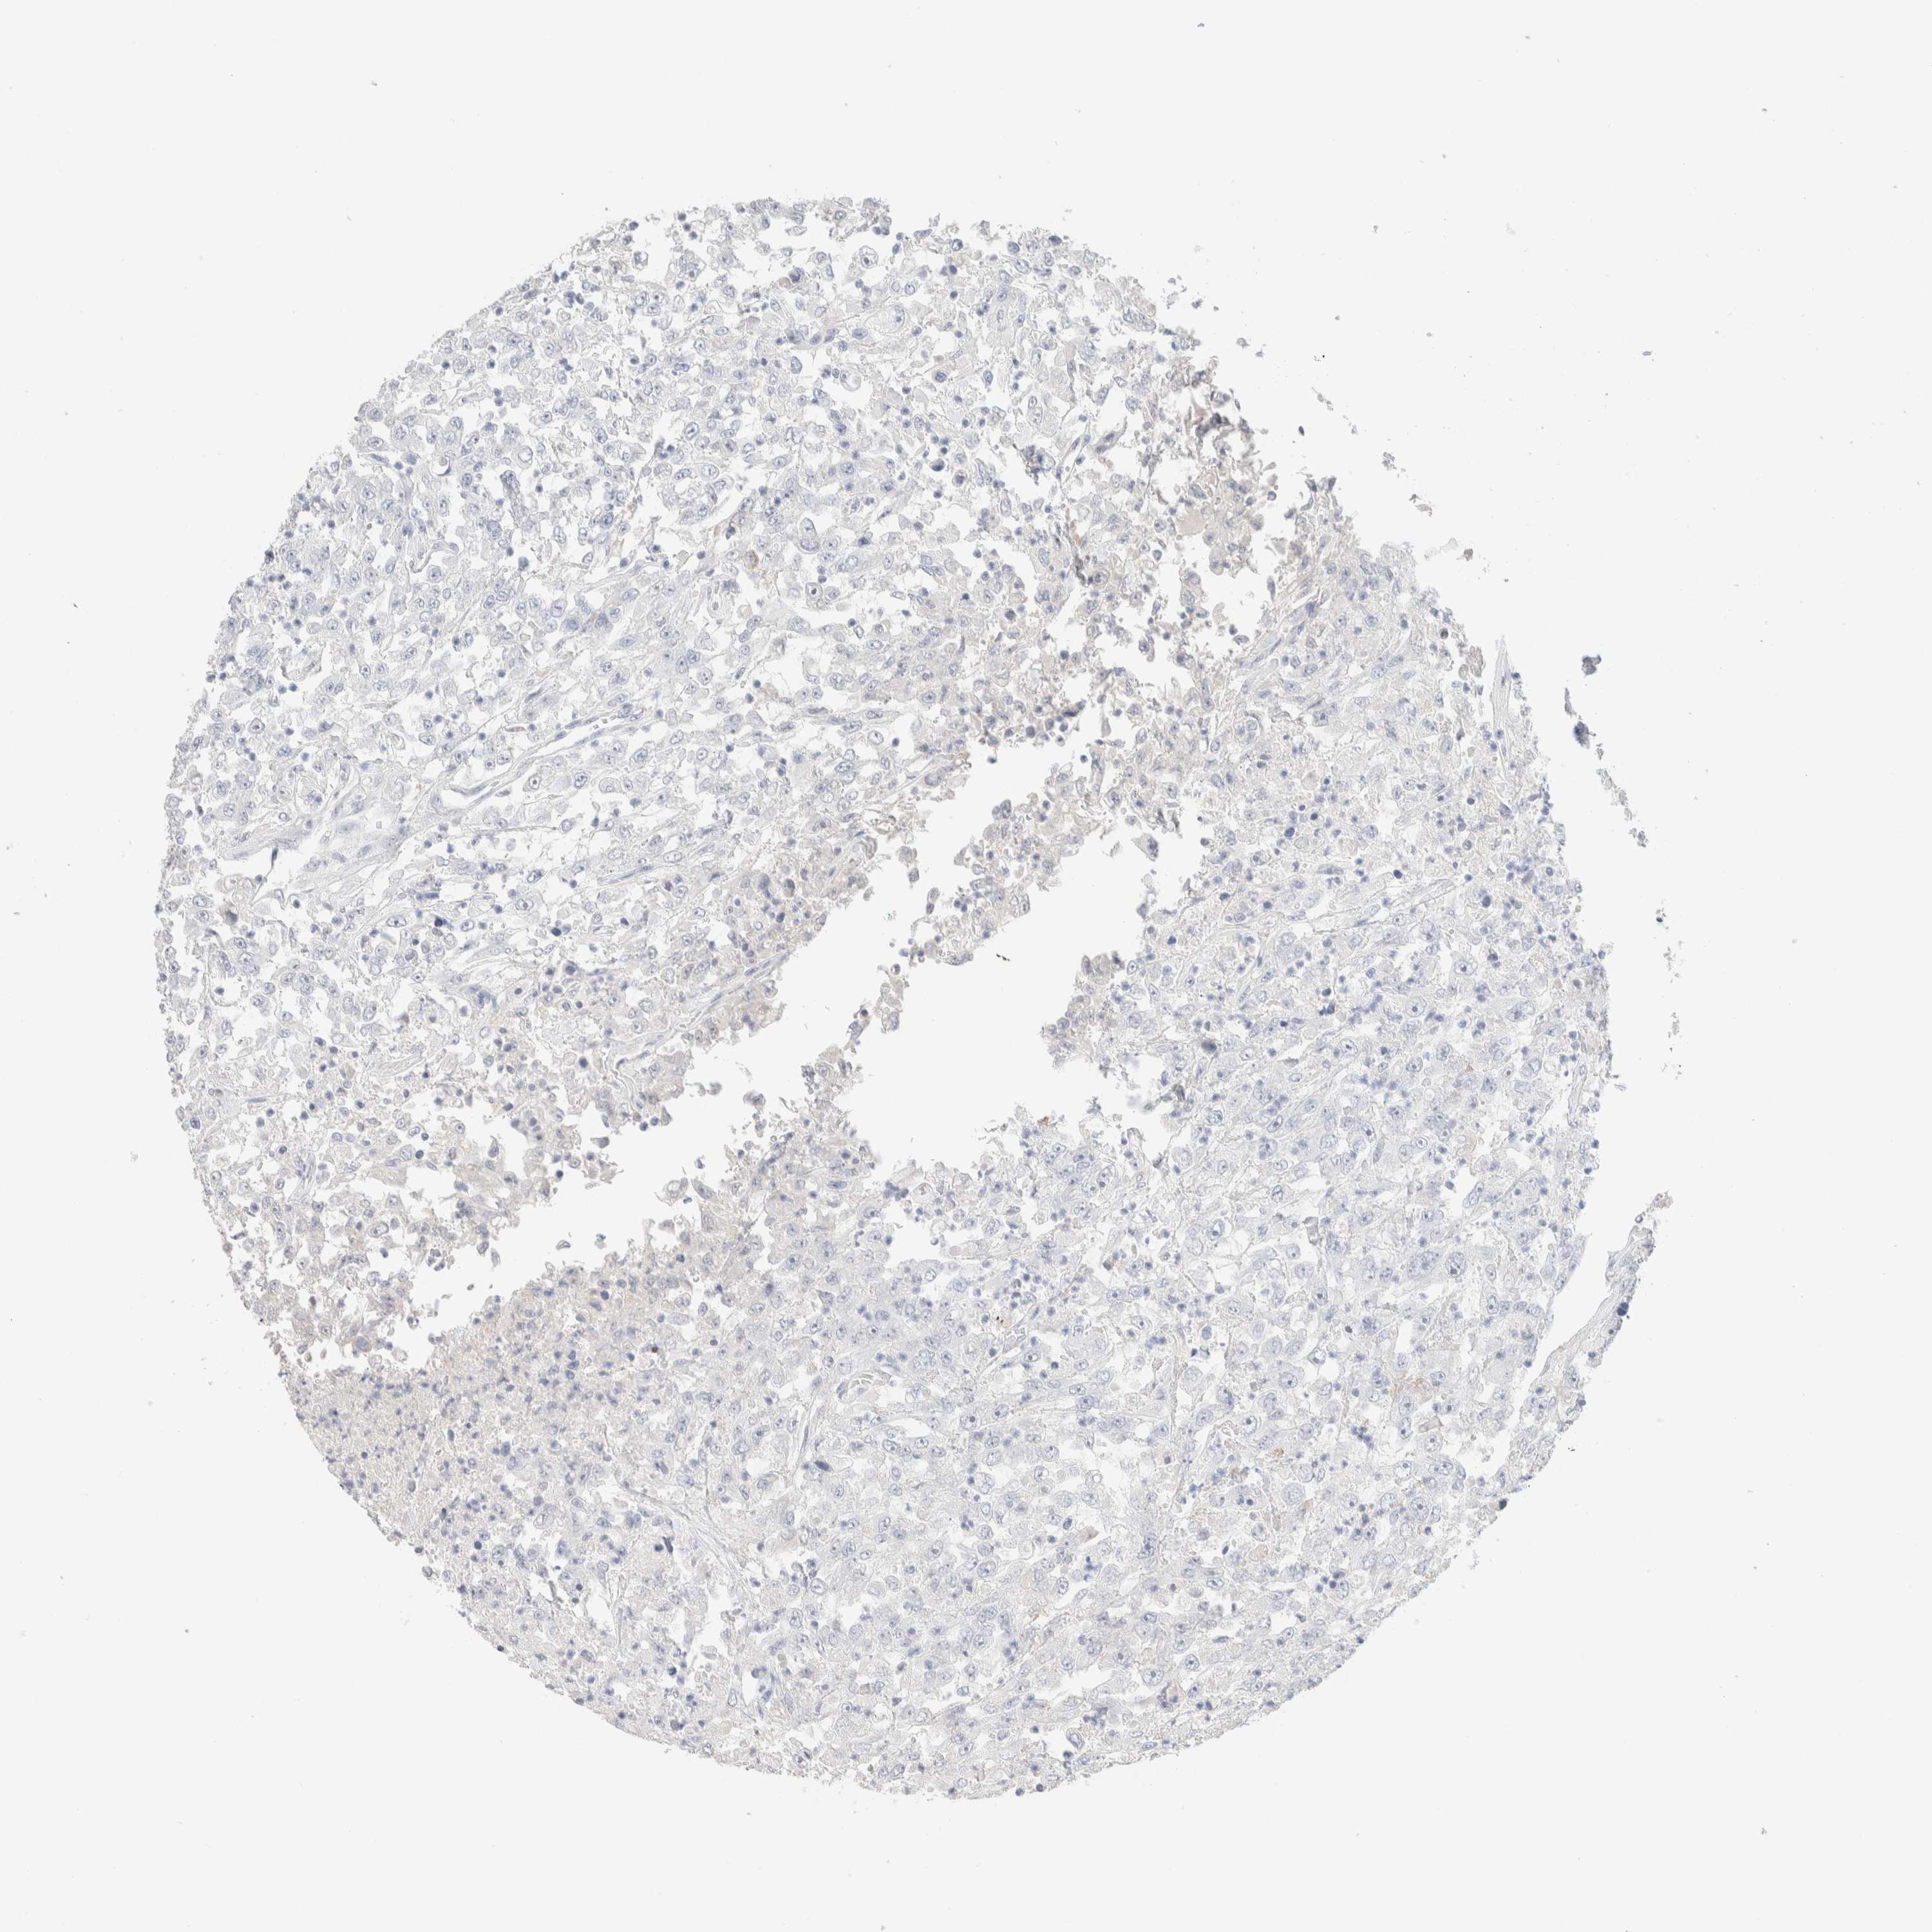

UROTHELIAL CANCER - Protein expressioni

A mouse-over function shows sample information and annotation data. Click on an image to view it in a full screen mode. Samples can be filtered based on level of antibody staining by selecting one or several of the following categories: high, medium, low and not detected. The assay and annotation is described here.

Note that samples used for immunohistochemistry by the Human Protein Atlas do not correspond to samples in the TCGA dataset.

Antibody stainingi

Antibody staining in the annotated cell types in the current human tissue is reported as not detected, low, medium, or high, based on conventional immunohistochemistry profiling in selected tissues. This score is based on the combination of the staining intensity and fraction of stained cells.

Each image is clickable and will lead to virtual microscopy that enables deeper exploration of all samples and also displays staining intensity scores, fraction scores and subcellular localization as well as patient and tissue information for each sample.

Antibody HPA022856

Antibody HPA023489

Urothelial carcinoma, Low grade

Urothelial carcinoma, High grade